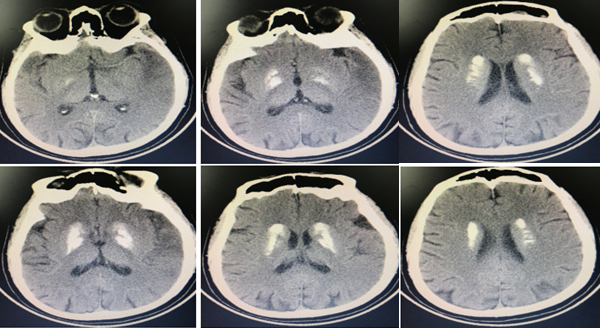

病例8

患者男,13岁,右上肢麻木、活动笨拙 3月余。

答案:生殖细胞瘤。生殖细胞瘤可发生于中线部位(松果体或鞍上区)、纵隔或骶尾区等其它部位;突出临床表现是内分泌紊乱,表现为上视障碍和性早熟,同时可伴有下丘脑功能障碍,如尿崩、烦渴、嗜睡及肥胖;生殖细胞瘤有特定发生部位和高的钙化发生率,是确诊的主要依据。患者头部CT如下: